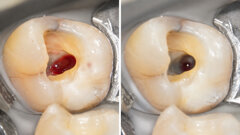

Matériaux de restauration sans amalgame

Les alternatives à l'amalgame comprennent les matériaux à base de verre hybride et les ciments verre-ionomère à haute viscosité. Chaque alternative présente des avantages et des inconvénients uniques, et le choix dépend souvent des besoins spécifiques du patient, y compris des considérations esthétiques, des exigences de durabilité et des contraintes financières.

Le professeur Falk Schwendicke résume cette situation dans un article récent : « Il n'existe pas de matériau unique qui réponde à toutes les exigences d'un remplacement d'amalgame ; au contraire, une gamme de matériaux aux propriétés différentes est disponible, et les dentistes devront faire des choix éclairés pour déterminer quel matériau convient le mieux à telle ou telle indication ».

« L'ère de l'amalgame dentaire touche lentement à sa fin », conclut-il. Les percées dans le domaine de la technologie dentaire pourraient déboucher sur de nouveaux matériaux plus avancés pour les restaurations dentaires à l'avenir.